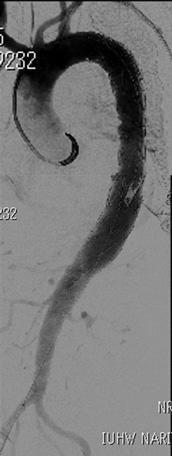

解離性胸腹部大動脈瘤に対する枝付きステントグラフト